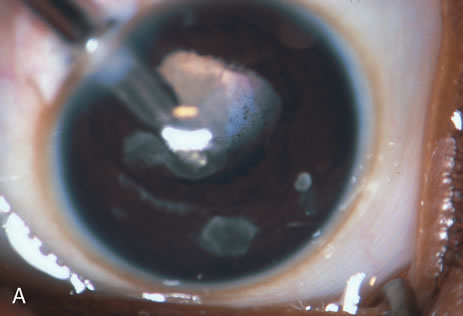

The most common application of the Nd:YAG laser in ophthalmology has been to open an opacified posterior lens capsule. The opacified capsule is commonly referred to as a secondary membrane (Fig. 6). A capsulotomy is recommended when there is a decrease in visual acuity that is due to opacification of the posterior lens capsule. This can cause either partial or complete obstruction of the visual axis. Judging the extent of a capsule's opacity and its effect on the patient's visual development may be difficult, especially in young or nonverbal children or in the presence of amblyopia. Signs that vision is decreased in a child are decreased light reflex on retinoscopy, presence of an ocular deviation, usually esotropia; decreased visual function; failure of the visual acuity to improve with occlusion; and a reduction in vision in spite of occlusion and accurate correction of the refractive error. During the evaluation, it is important to exclude other causes of these signs. Once it has been determined that the posterior capsule of the lens is causing the vision to be decreased (even slight opacity that decreases acuity to 20/30 or 20/40), photodisruption or opening of the posterior capsule is indicated.

Fig. 6. This child developed a secondary membrane after cataract surgery. The posterior capsule was not opened at the time of surgery.

Streak retinoscopy, performed with the pupil well dilated, is helpful in determining the degree of opacification. In severe degrees of opacification, the red reflex may be diminished or absent. The posterior capsule can also be examined by using a slit lamp or by using the indirect ophthalmoscope as a light source and holding a 20D indirect lens close to the eye so that it serves as a magnifying lens. The hand-held portable slit lamp and the direct ophthalmoscope are other methods available to confirm the location and extent of opacification. These techniques are also used to judge the thickness of the secondary membrane. In children, the secondary membranes tend to become thicker with time. Estimation of the degree of thickness is important, because the thicker the membrane, the more energy it will take to photodisrupt it. Also, thick membranes will not retract as much as thin membranes. If the posterior capsule is thickened or the opacity is very dense, capsulotomy will need to be performed with either a discission knife or a vitreous suction-cutting device. Atkinson and Hiles suggested that the procedure should be performed within 3 weeks of the cataract surgery. Longer delays result in thicker membranes that require higher energy applications to perform the treatment. Recurrent membranes must be anticipated. In Atkinson's series, eight of 28 membranes required retreatment.29 When membranes recur, they are treated by repeating the procedure.